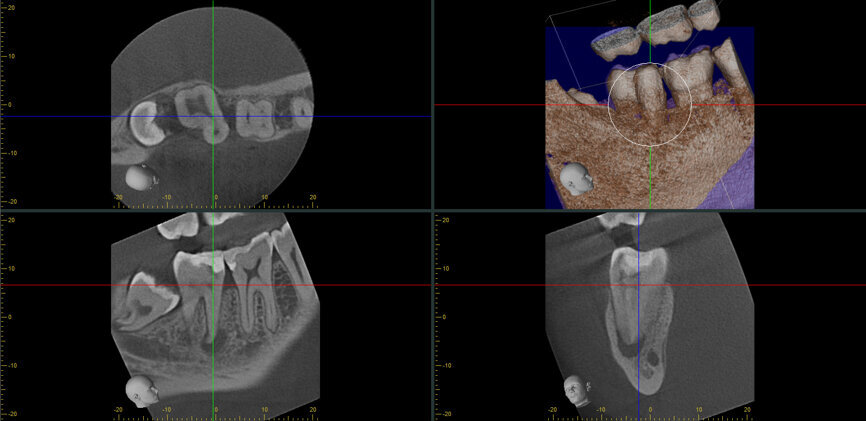

Fig. 14a: Case treated with Bassi Logic controlled memory nickel titanium files. Note the visualization of the third root on this lower molar and conservative canal preparation shape. (Courtesy of Dr. Alex Chan)

Fig. 14b: Case treated with Bassi Logic controlled memory nickel titanium files. Note the visualization of the third root on this lower molar and conservative canal preparation shape. (Courtesy of Dr. Alex Chan)

Managing complex anatomy is much simpler if the clinician has a pre-operative road map. The CBCT provides the roadmap and the surgical microscope the lens (literally) through which to visualize the result. Aside from a relaxed patient who is profoundly numb, being able to visualize anatomy by taking a pre-operative (and possibly intra-operative) CBCT and using a surgical microscope during treatment have no substitutes. They are the current “Gold Standard” in that 3-D imaging shows the clinician the true reality of a clinical situation as opposed to the suggestion gained from a 2-D radiograph. Proper interpretation of imaging prior to and/or during endodontic treatment goes a long way in taking the “guesswork” out of identifying canal location and other anatomical complexities as the procedure unfolds. In a 2014 study by El Fayad and Johnson, it was determined that when having a pre-operative CBCT as compared to 2-D radiographs alone, the treatment plan was modified 62 percent of the time. This is a huge game changer to think that the information learned from 3-D imaging changed the plan of treatment over six times out of 10 (Fig. 4).[2]